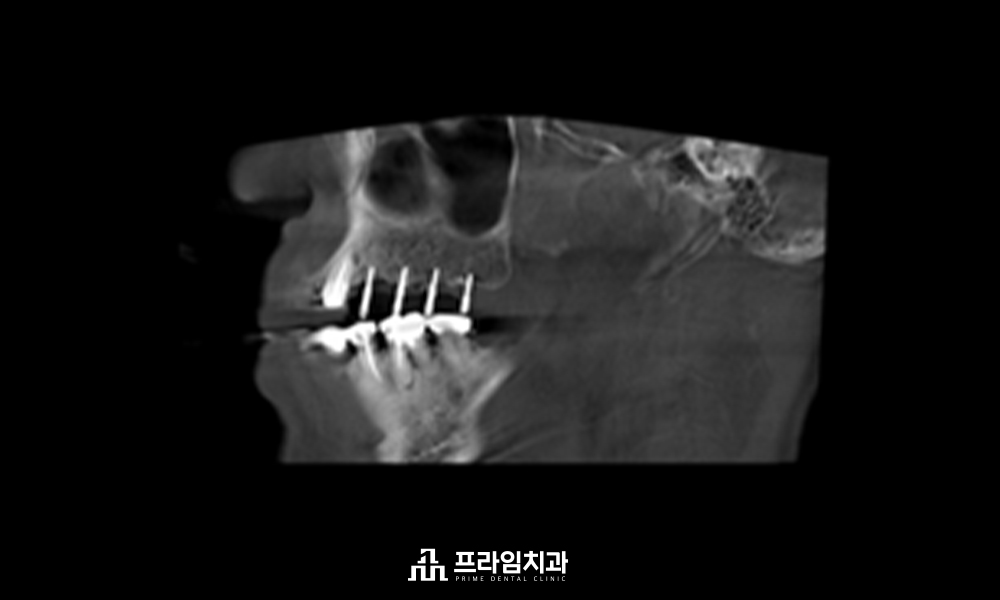

저희 치과에서는 임플란트

식립 전 3D CT와 구강 스캐너를

활용하여 육안으로 판단하기

힘든 구강 해부학적 구조물과

혈관 및 신경의 위치까지 면밀히

파악하여 1:1 맞춤 치료 계획을

수립하고 있습니다.